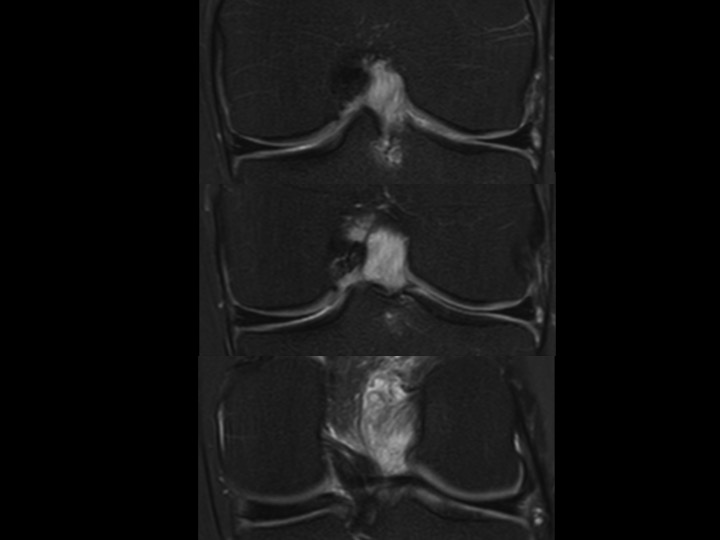

44M worsening knee pain

There is diffuse intrasubstance mucoid degeneration and expansion of the ACL with only small septated ACl ganglion near the femoral origin. This is typically seen in older individuals, but I like to think this gentleman is quite young. No other pathology on MRI. Apparently treatment is varied; Ive only found small series with good outcomes, but no mention of time to clinical follow up. It seems in this case that judicious debridement would be difficult, as the entire ligament seems to be rotten to the core. Reference article.

anterior cruciate ligament ( RID2781 )